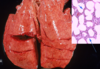

This is a lung from a cow. What are these lesions due to?

bovine respiratory syncytial virus